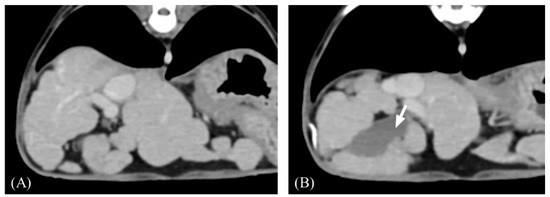

3.2. Qualitative Computed Tomographic Features